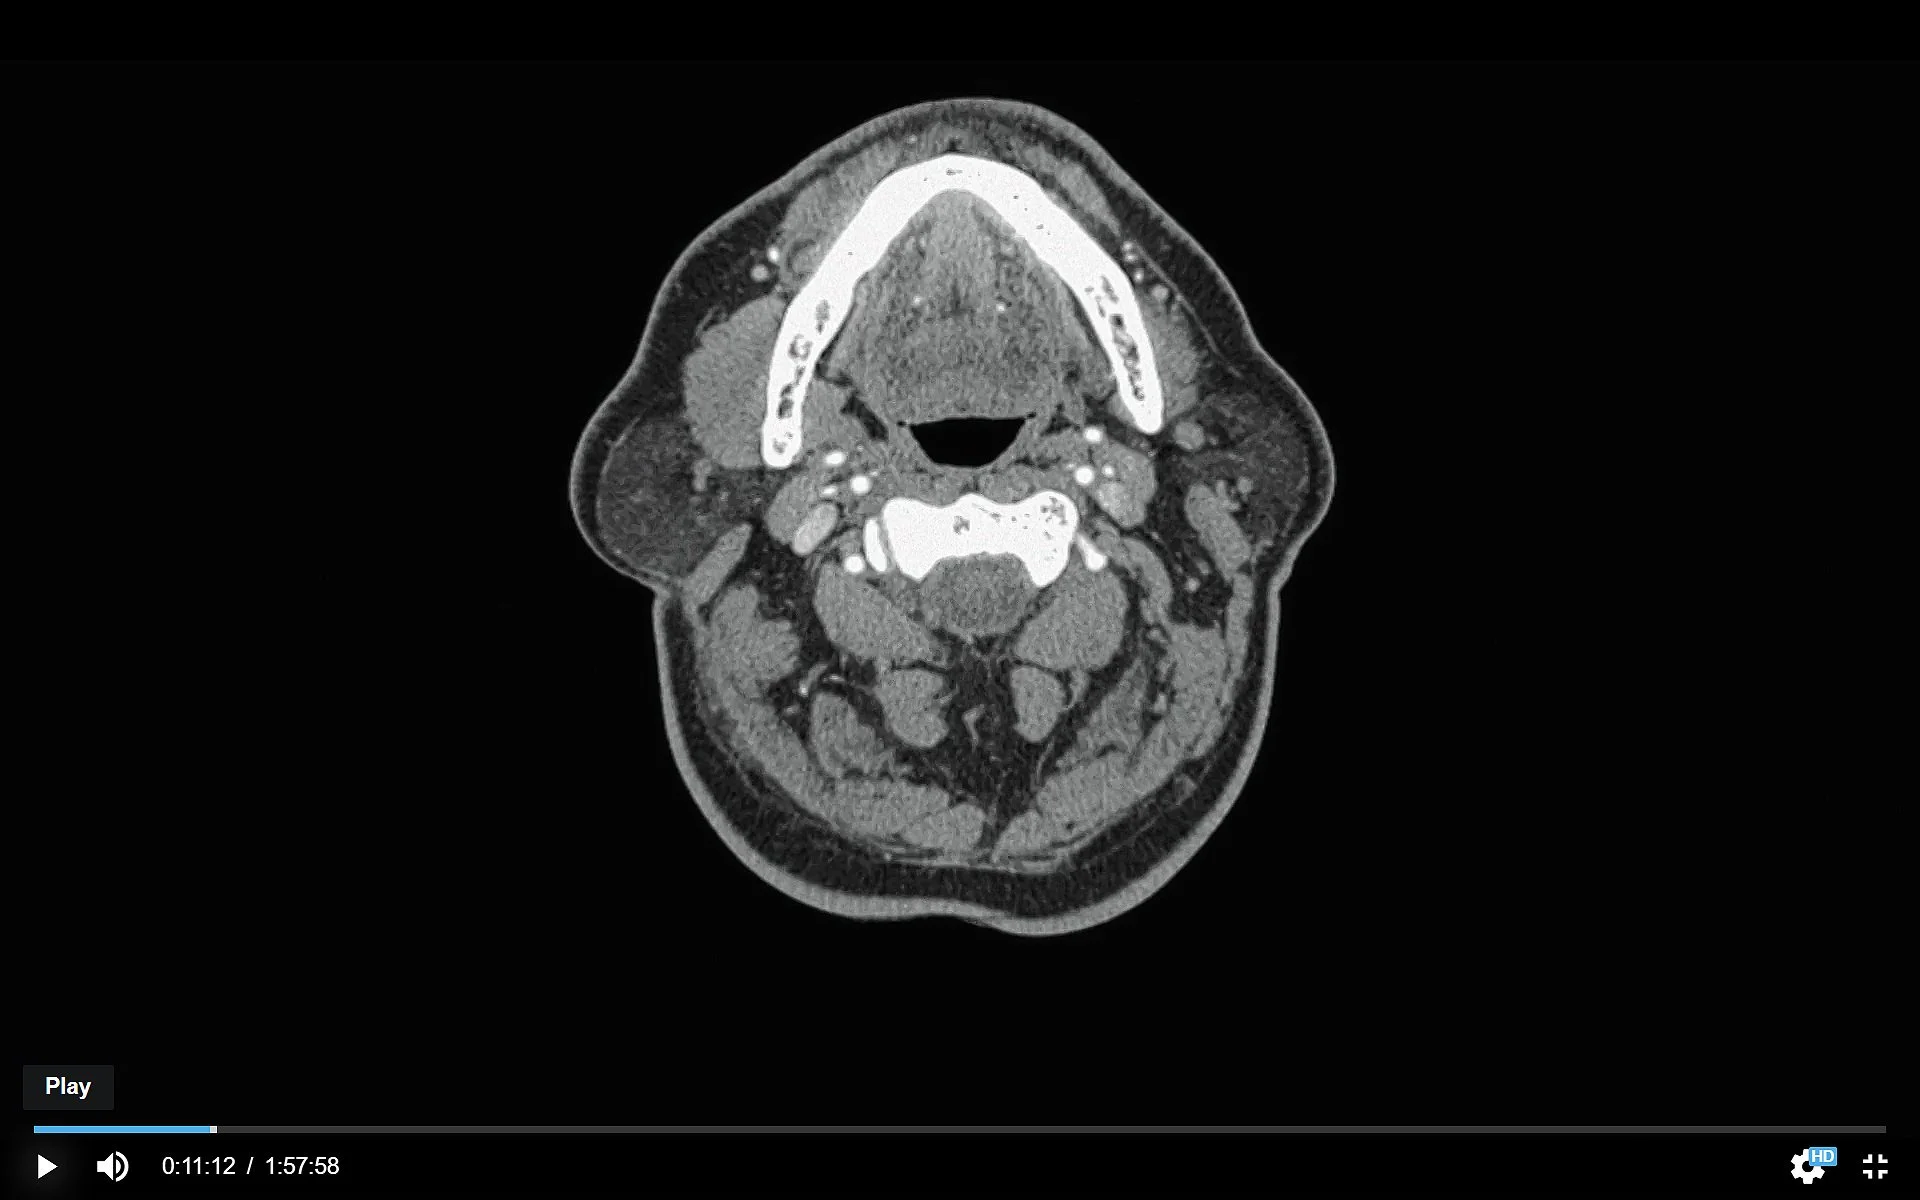

The single shot which is most clearly emblazoned on my memory is the shot of the scalpel cutting open the pregnant woman’s belly for a Cesarean. The doctors pull the opening apart with apparent violence, reaching in to scoop out the baby, who is, thankfully, very small but apparently healthy. The mother indicates that she still has sensation in her belly and feel the pinchers when they touch her, but she makes no sound, so we have no idea what sort of pain she is feeling, or if she is feeling anything at all.